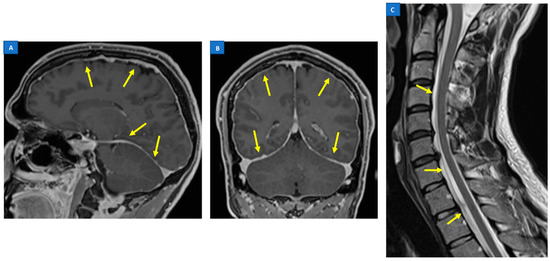

5.1. Head MRI

6. Differential Diagnosis between SIH and Chiari Malformation Type I